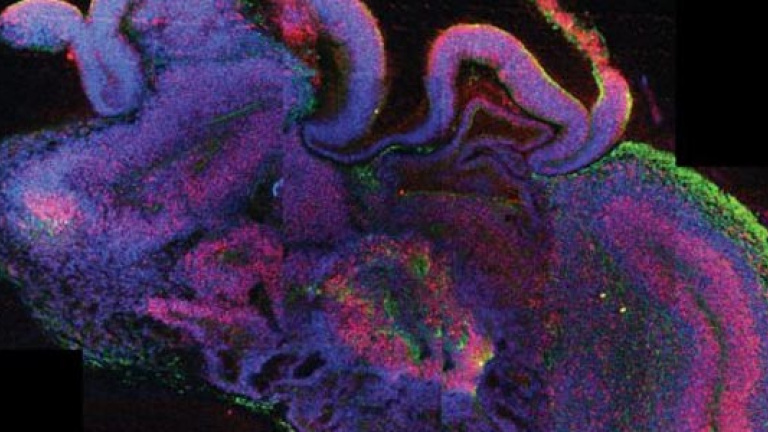

Un equipo de científicos europeos ha desarrollado pequeños cerebros humanos tridimensionales, de cuatro milímetros de diámetro, del tamaño de un guisante, a partir de células madre pluripotentes que ayudarán a profundizar en el estudio de las enfermedades neurológicas, informó este miércoles la revista científica Nature.

"Este planteamiento puede superar algunas de las limitaciones que encontramos cuando experimentamos con el cerebro de los animales, ya que no comparte las mismas peculiaridades del cerebro humano", añadió el científico. Estos microcerebros, que incluyen la corteza cerebral que cubre los dos hemisferios, están formados por diferentes tejidos dispuestos en capas, cuya organización guarda muchas semejanzas con la de un cerebro en sus etapas más tempranas de desarrollo.

A partir de células madre pluripotentes, el equipo de investigadores añadió al sistema inicial una serie de células procedentes de pacientes que padecían microcefalia para obtener un cerebro característico de una persona con esta enfermedad. Los científicos encontraron así que en los cerebros con esta dolencia las células precursoras de las neuronas dejaban de proliferar demasiado pronto, un defecto que podría explicar algunas de las causas de la microcealia.